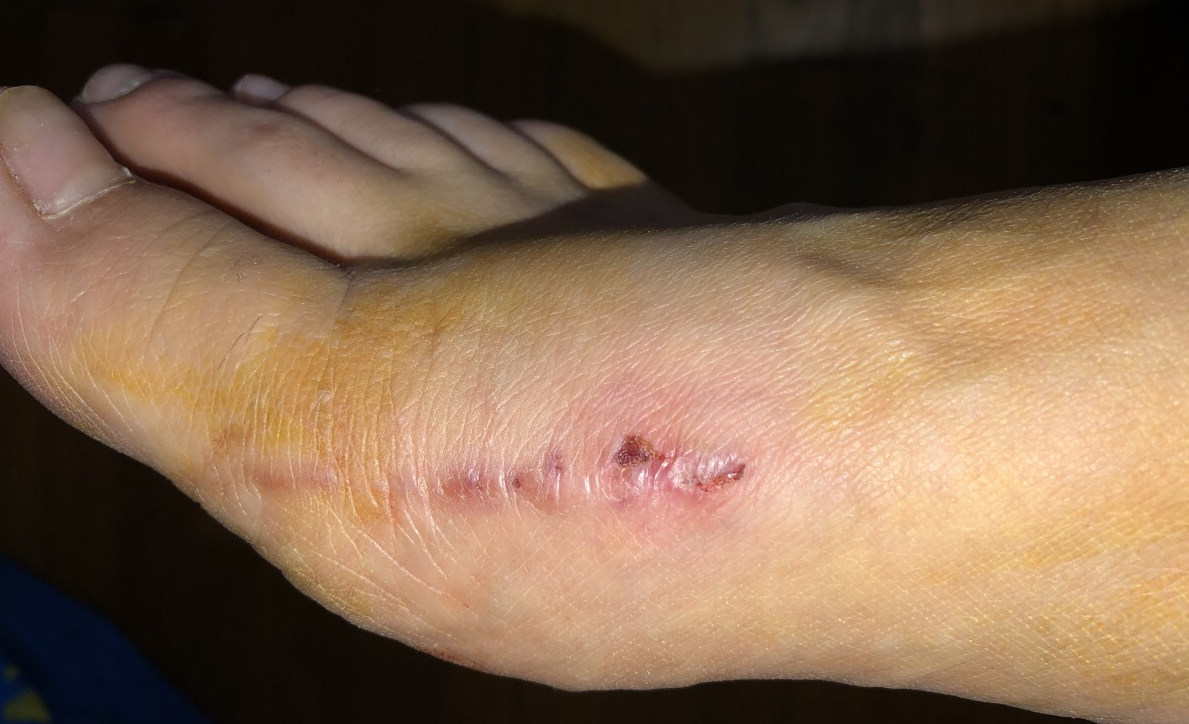

My Foot One Month After Surgery

The surgery was done under general anesthesia, and I couldn’t move for an entire day afterward. I felt nauseous, dizzy, completely out of it. For the next three days, I was basically glued to the couch — it felt like a herd of elephants had trampled over me. Even going to the bathroom was a struggle. A nurse had to assist me, and the look on her face said it all — she clearly found the whole situation unpleasant. I was mortified. The only thing that gave me a sliver of relief was thinking the bunion was finally gone and I could put this behind me. Unfortunately… things weren’t that simple.

I wasn’t even allowed to walk for the first week. During that time, the pain was intense, and the painkillers barely made a difference. After seven days, they sent me home — not because I was healed, but because they couldn’t keep me there any longer without charging me. After two weeks that felt like prison, all I could dream about was taking a shower in my own home and finally relaxing. But even that wasn’t easy. I had to wrap my foot in plastic or foil to keep water from getting on the stitches.